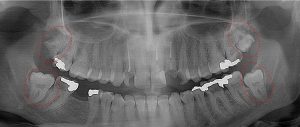

This 19 year old patient has all four 3rd molars present (circled). The roots are +90% formed. Both lower 3rd molars are impacted against the 2nd molars with no chance of further eruption and a +60% probability of decaying before age 30. The patient presented with pain and infection around both lower 3rd molars, requiring immediate extraction